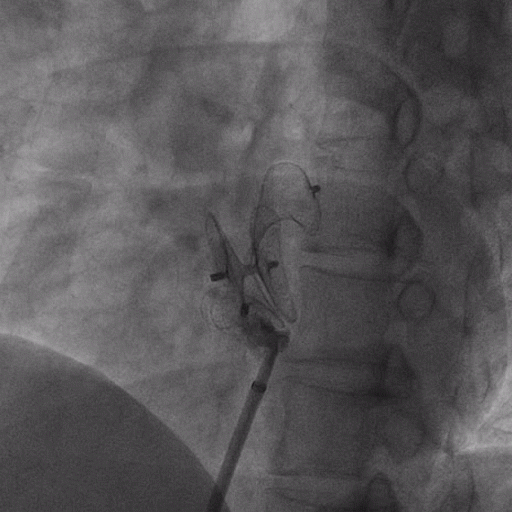

在獲得患者同意后,1月12日,尚福軍主任為患者進(jìn)行了PFO封堵術(shù)。術(shù)中造影可見封堵器殘余漏,尚福軍主任用精湛的技藝,順利通過(guò)封堵器殘余漏裂縫,將右心導(dǎo)管從右房送入左房,且順利到達(dá)肺靜脈;遂行卵圓孔未閉封堵術(shù)后殘余漏再次封堵;且完美釋放PFO封堵器,可見兩封堵器呈“馬蹄蓮”狀,再次術(shù)中造影未見殘余漏。